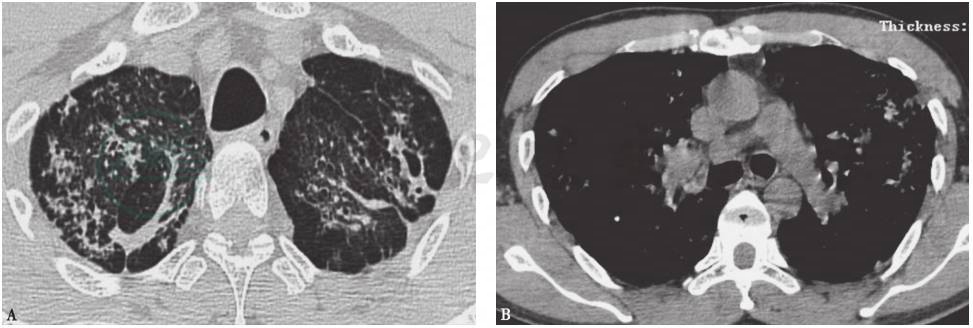

图2 肺结核胸部影像学表现

胸部CT可见双上肺弥漫小结节病灶,小结节有融合趋势,伴空洞形成和纤维索条

肺结核:严重肺结核的临床表现可有呼吸困难,但常伴有咳嗽、咳痰、乏力、盗汗、消瘦、午后低热等,影像学表现特点为病灶大多累及上叶尖后段和下叶背段,大小、形态不一,可为结节影、斑片影、实变影、卫星灶等(图2)。陈旧性肺结核病灶常可表现为钙化灶。本例患者否认结核病史,无结核高危因素(如免疫力低下、高血糖等),影像学检查示钙化部位广泛,两肺多叶、段均有累及,故因为结核可能性不大,可进一步检查结核抗体、痰抗酸杆菌涂片等相应指标以排除之。